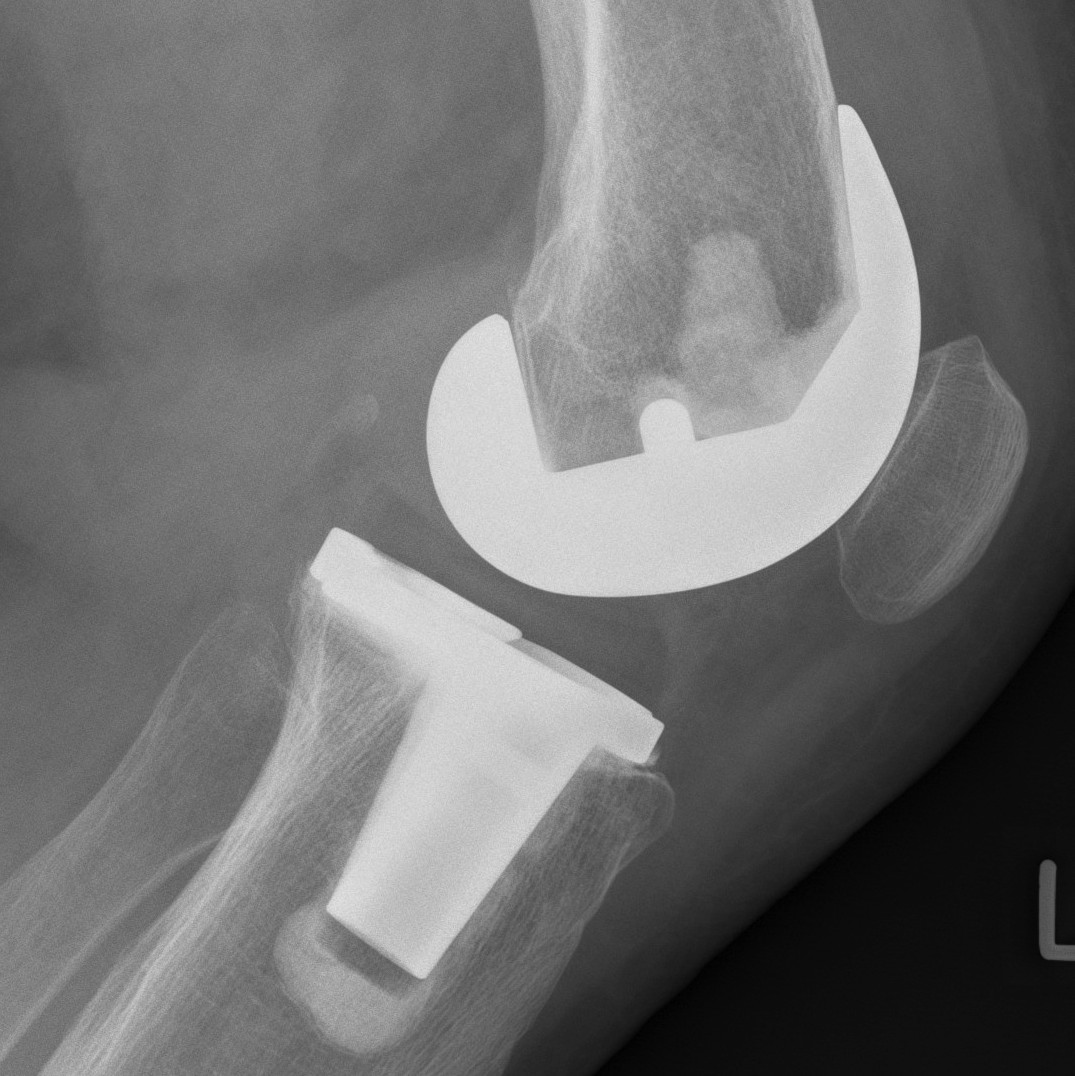

Design

1. Tibial PE post with a femoral cam

- femoral cam engages the post at a designed flexion point

- prevents femur translating anteriorly

- with further flexion get rollback

2. Deeply dished articular surfaces

- increased conformity

3. "Third condyle"

- limits excessive tibial translation